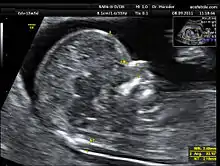

![]() Translucencia nucal en la semana 13 | ||

La translucencia nucal consiste en la medición de un espacio sonoluscente o econegativo situado en la zona posterior de la nuca del feto. El momento adecuado para realizar esta medición es la semana 12 aunque puede realizarse entre las semanas 11 y 14 del embarazo.

Para realizarse correctamente el calliper o cursor ecográfico se debe posicionar en las partes internas de los ecos que definen la sonoluscencia. La ecografía debe realizarse vía abdominal aunque pueden obtenerse las imágenes también vía vaginal.